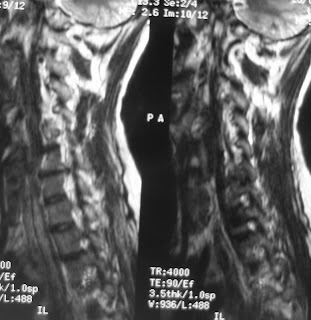

24-5-2011, C6-7